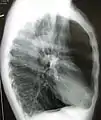

A chest X-ray is not useful to establish a diagnosis of COPD but it is of use in either excluding other conditions or including comorbidities such as pulmonary fibrosis and bronchiectasis. Characteristic signs of COPD on X-ray include hyperinflation (shown by a flattened diaphragm and an increased retrosternal air space) and lung hyperlucency.[5] A saber-sheath trachea may also be shown that is indicative of COPD.[111]

A lateral chest X-ray of a person with emphysema: Note the barrel chest and flat diaphragm.